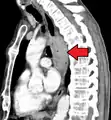

Esophageal cancer (lower part) as a result of Barrettʼs esophagus

Male predominance is particularly strong in this type of esophageal cancer, which occurs about 7 to 10 times more frequently in men.[25] This imbalance may be related to the characteristics and interactions of other known risk factors, including acid reflux and obesity.[25]